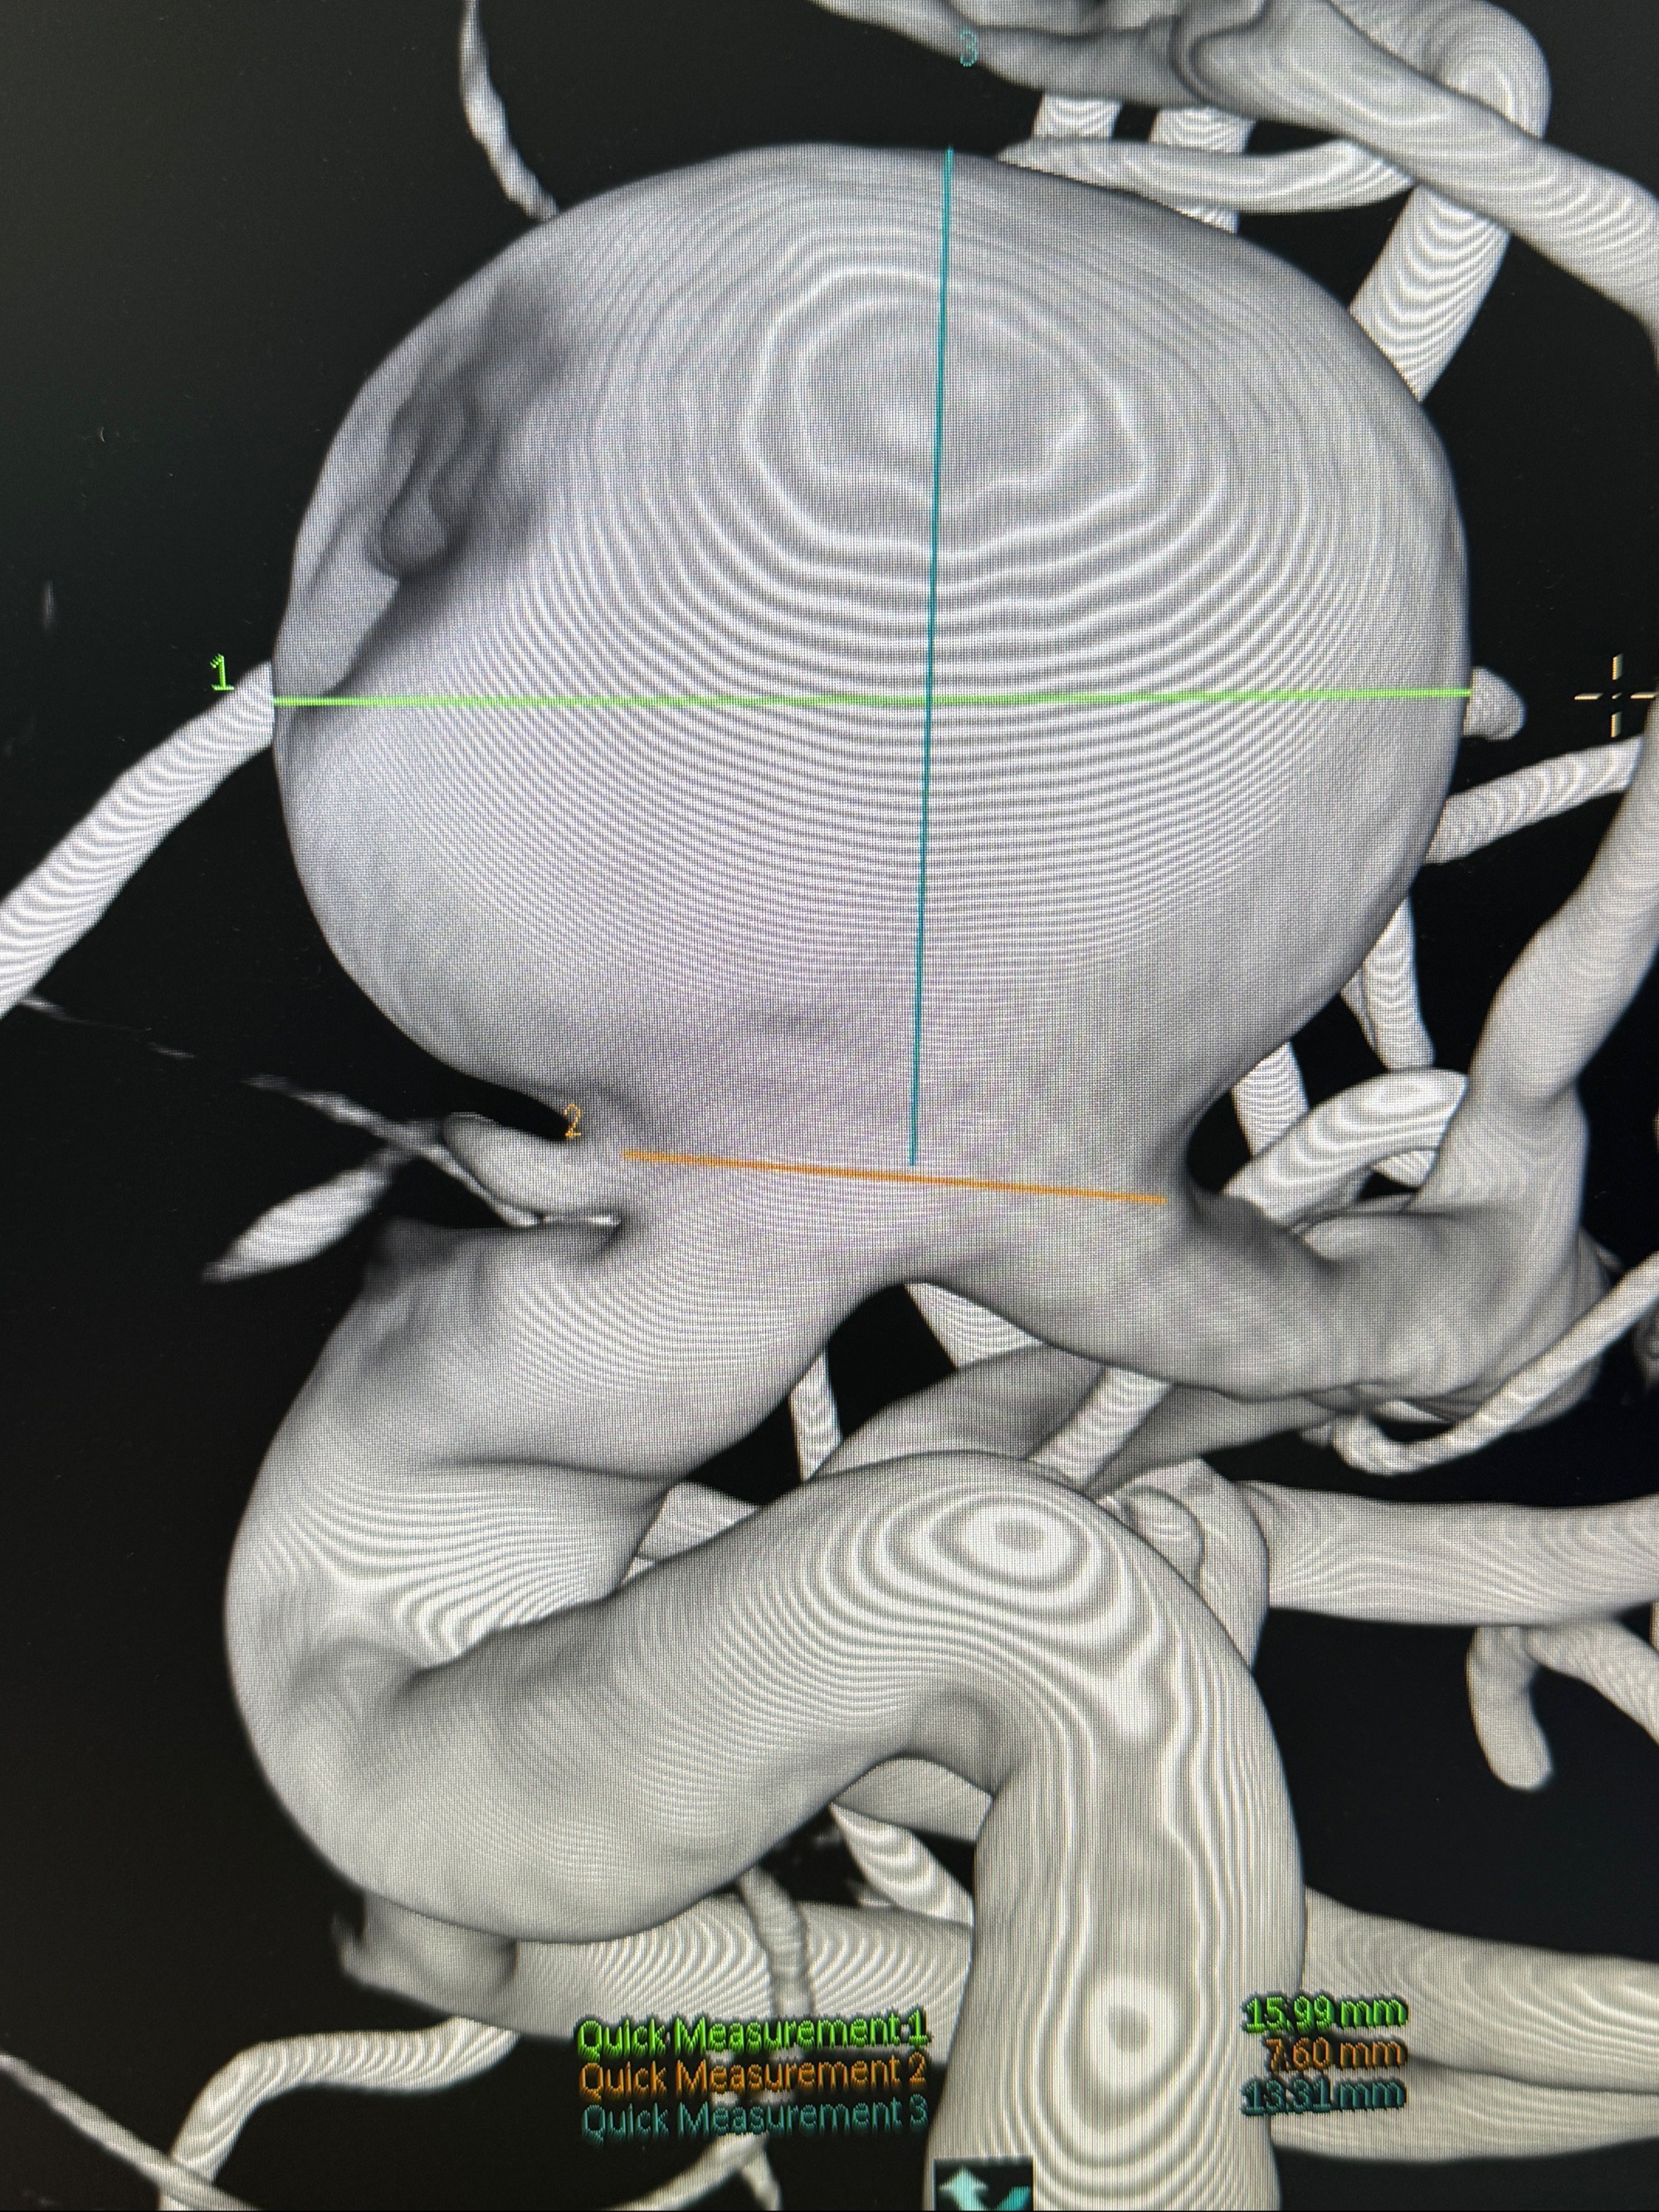

旋转3D展示动脉瘤局部的血管构筑

测量动脉瘤的大小:16*13.8*7.6mm大小,较原先变大,考虑双抗后瘤内血栓溶解可能

4.5-30mmTurbridge密网支架,于M1近心端打开

Tubridge 4.5-35mm